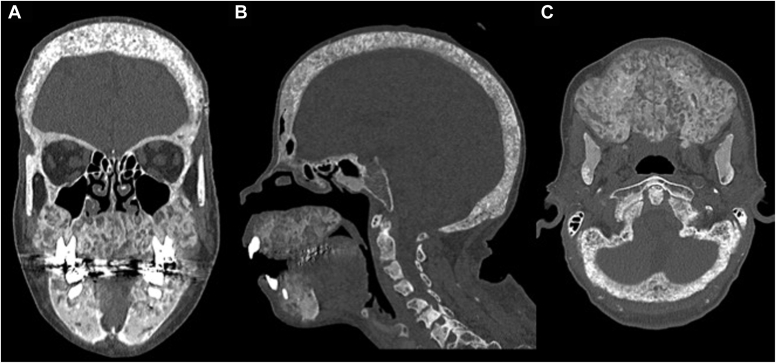

A 48-year-old woman with a history of hypertension, coronary artery disease, and ESRD on hemodialysis presented with severe secondary hyperparathyroidism and calciphylaxis. She had significant changes to her face in the last 3 months leading to oropharyngeal dysphagia and difficulty articulating. Physical examination revealed bony overgrowth in her upper jaw and hard palate, widely spaced teeth, and calcinosis cutis. Her parathyroid hormone (PTH), calcium, and phosphorus levels were 5066 pg/mL (normal range, 12-88 pg/mL); 10.0 mg/dL (8.4-10.2 mg/dL); and 5.4 mg/dL (2.7-4.5 mg/dL); respectively. Using a multidisciplinary approach, she successfully underwent a 3.5-gland parathyroidectomy (immediate postoperative PTH level, 600 pg/mL). She was discharged without complication. Pathology showed hypercellular parathyroid glands with reactive changes.

ULO, the most severe form of renal osteodystrophy, results in hypertrophy of the craniofacial skeleton. It carries the risk of significant comorbidities due to cranial nerve compression, respiratory compromise, dysarthria, and dysphagia.